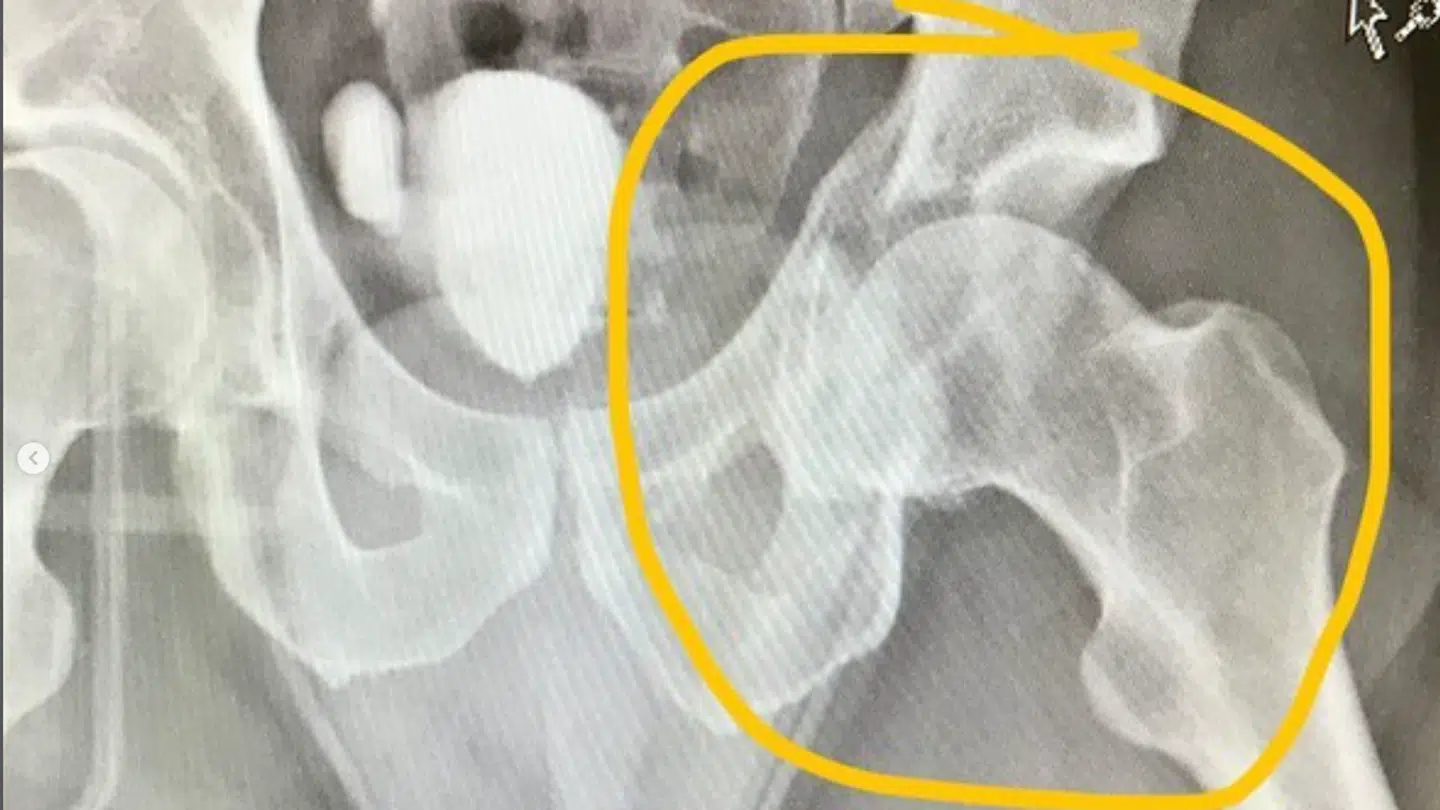

Efter styrtet blev det konkluderet, at Nicki Pedersen ikke kun have slået benet, men at hoften og bækkenet var brækket. Derfor er den danske stjerne endnu ikke stabil nok til at kunne drage mod Odense, hvor han skal opereres, selvom han får smertestillende.